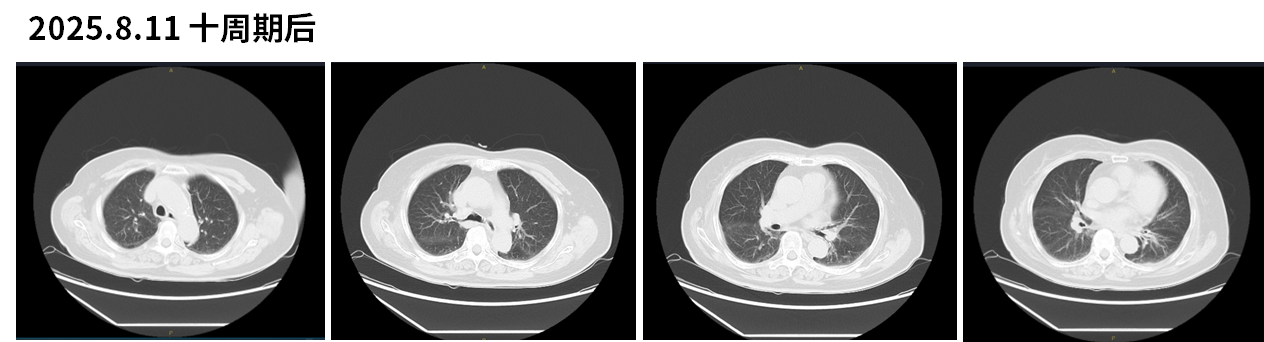

• 依沃西单抗单药治疗2周期后,患者症状明显缓解,治疗6周期达PR,治疗过程中未出现明显药物相关不良反应。

图4 依沃西单抗治疗6周期后CT结果

图5 依沃西单抗治疗10周期后CT结果

该患者为85岁高龄女性,因“咳嗽、气急半月余”入院,经院内外系统评估后确诊为左肺腺癌(cT4N3M1b,IVA期),驱动基因阴性,PD-L1表达水平高达60%。考虑患者年龄较大、基础情况不适用化疗,一线治疗选择依沃西单抗单药方案,自2024年11月28日起接受治疗。

疗效评估显示,仅2个周期后患者症状即明显缓解,6周期后影像学提示肿瘤显著缩小,达部分缓解(PR);同时血清肿瘤标志物CEA由峰值的13.5 ng/mL下降至3.55 ng/mL提示生物学应答明确。整个治疗过程中未出现明显药物相关不良反应,患者耐受性良好。目前治疗持续进行中,截止最新随访时间(2025.11.17),患者接受依沃西单抗单药一线治疗PFS已接近一年。